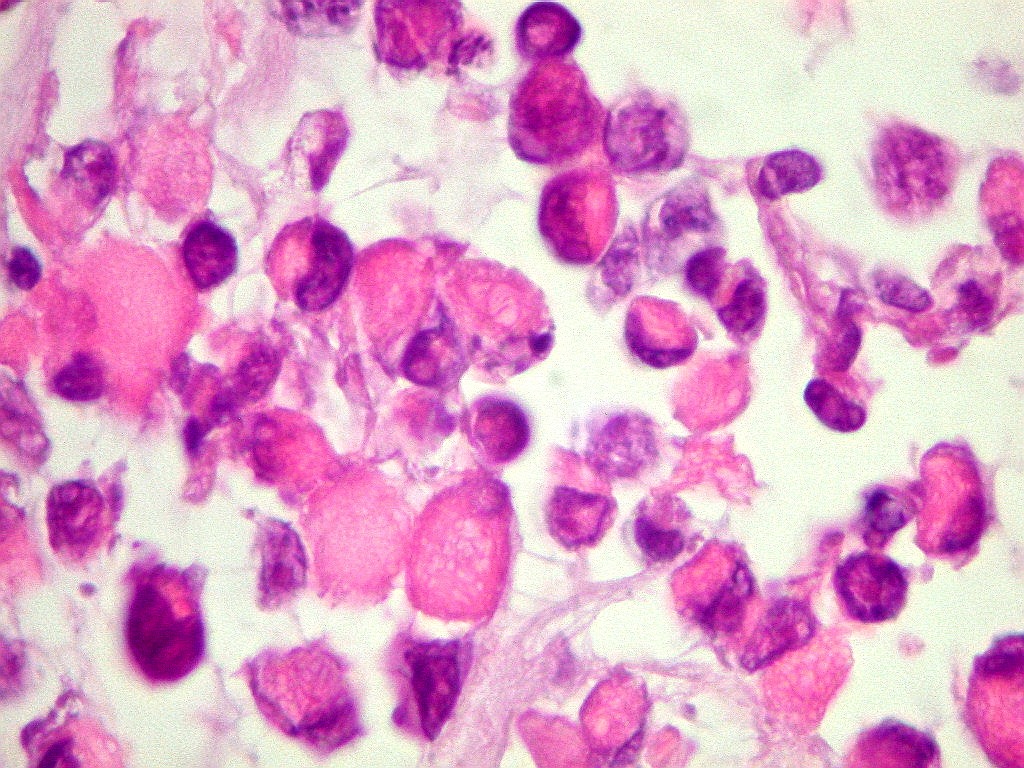

| HHF-35

Actina sarcomérica, positiva nas células neoplásicas.

Indica diferenciação muscular. |

Desmina.

Filamento intermediário de fibras musculares esqueléticas. |